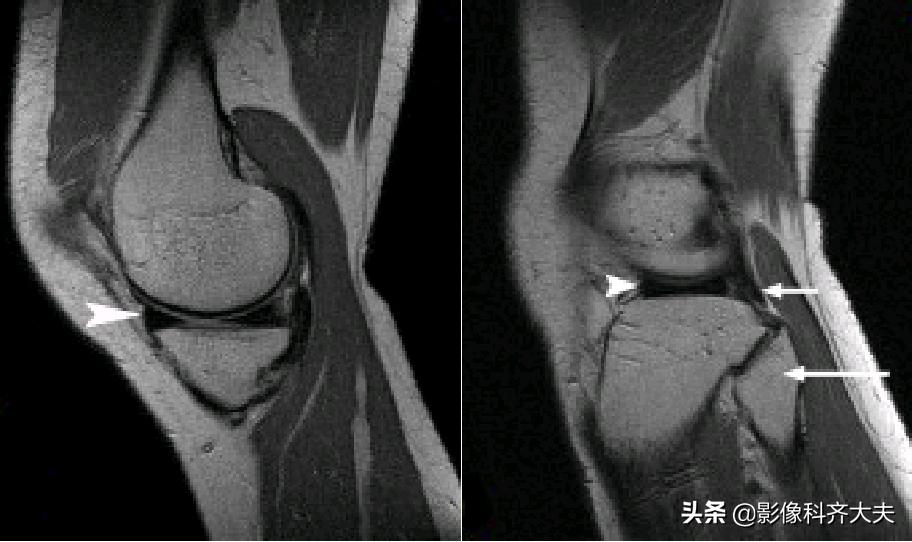

正常半月板MRI矢状位图像